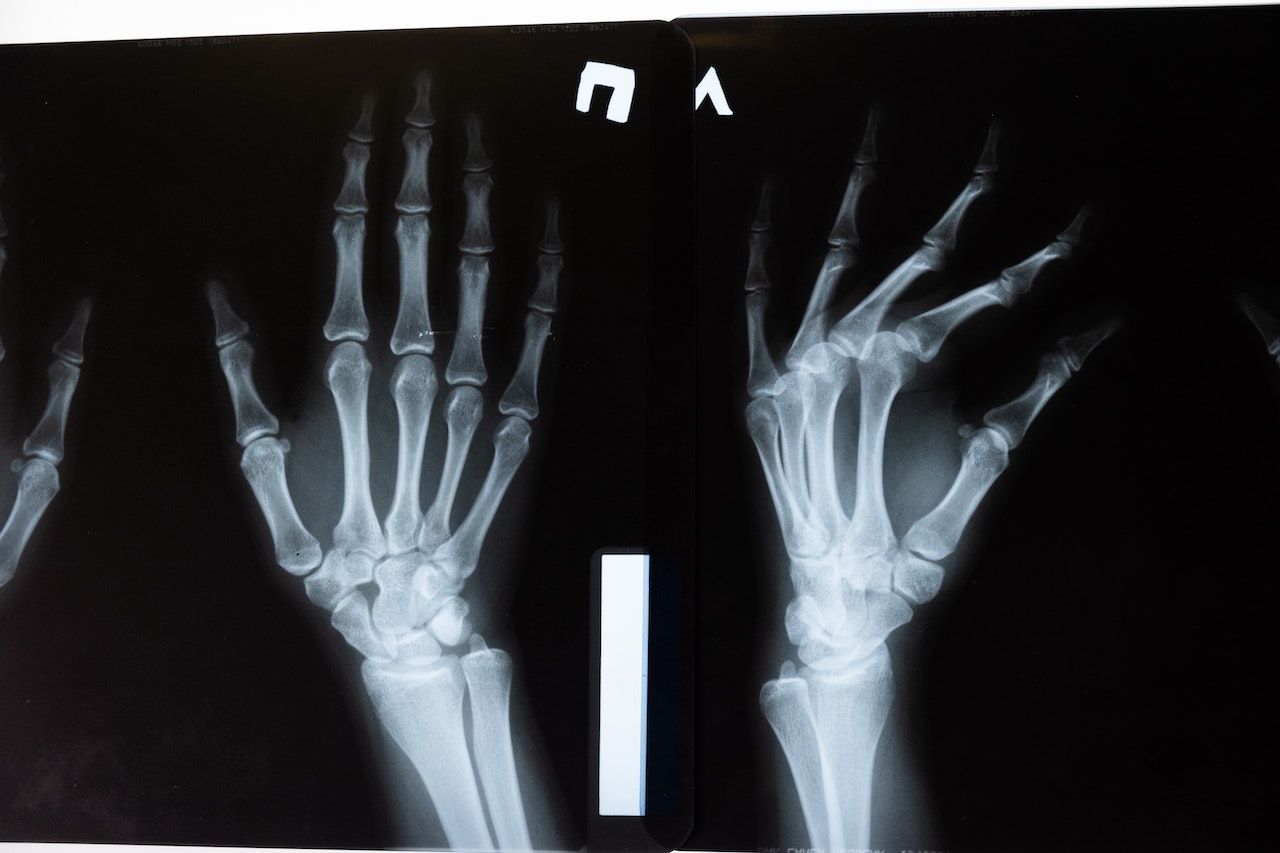

Quando si verifica una frattura del polso, i sintomi sono percepibili sia visivamente che fisicamente. Il polso appare gonfio e dolorante soprattutto alla palpazione. In questi casi è necessario recarsi in ospedale per effettuare una radiografia che potrà confermare o meno la diagnosi.

Dopo aver effettuato una radiografia, o in caso di bisogno di ulteriori dettagli, una tomografia computerizzata, viene identificato il tipo di frattura e di conseguenza, si potrà valutare se è possibile procedere con o senza intervento chirurgico.